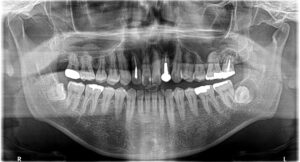

患者さんは50代男性。左上前歯の歯茎から膿が出るのを主訴に来院されました。

パノラマ撮影を行うと…

3つの大きな嚢胞が映ってきました(;゚Д゚)

①上顎左側側切歯根尖部に100円玉ぐらいの歯根嚢胞を認めます。

②上顎左側第二大臼歯根尖部に1円玉ぐらいの歯根嚢胞を認めます。

③下顎左側智歯周囲に500円玉くらいの含歯嚢胞を認めます。